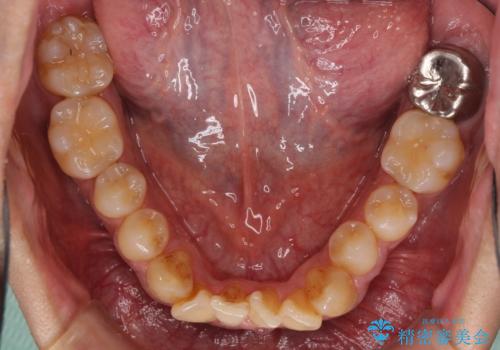

- 上下前歯の叢生を気にして来院された患者様です。

奥歯はクロスバイトとなっているので上顎は側方拡大を行いつつ、上下全体の叢生をインビザラインにより改善することとしました。

治療途中でクリーニングやホワイトニングを行い、歯列が整うと同時に明るい口元となりました。